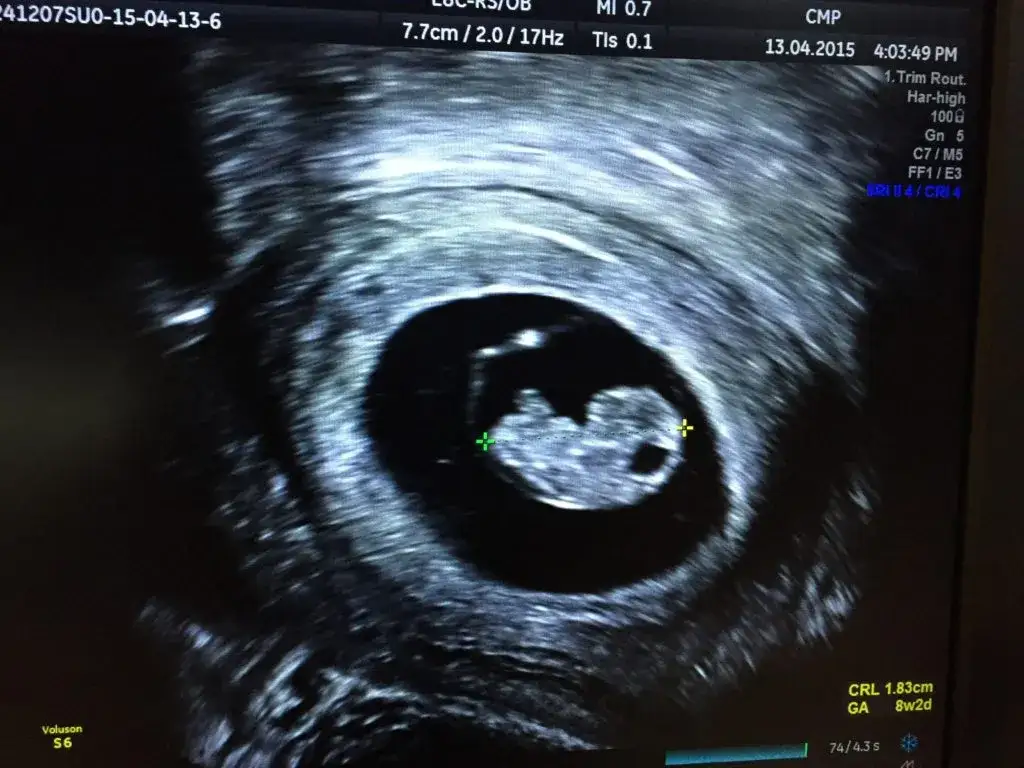

Biorąc pod uwagę wszystkie metody diagnostyczne, wizyta u ginekologa w celu potwierdzenia ciąży ma największy sens między 6. a 8. tygodniem ciąży. W tym czasie w badaniu USG dopochwowym zazwyczaj widoczny jest już pęcherzyk ciążowy, pęcherzyk żółtkowy, a co najważniejsze zarodek z wyraźnie bijącym sercem. To właśnie widoczna akcja serca jest ostatecznym, niepodważalnym potwierdzeniem żywej ciąży.

Badanie USG jest znacznie dokładniejsze i bardziej obiektywne niż badanie manualne, ponieważ pozwala na bezpośrednią wizualizację struktur wewnątrz macicy. Dzięki ultradźwiękom lekarz może zobaczyć pęcherzyk ciążowy, zarodek, a nawet usłyszeć bicie serca. To eliminuje subiektywne odczucia i dostarcza twardych dowodów na obecność ciąży.

Około 4-5 tygodnia ciąży (licząc od pierwszego dnia ostatniej miesiączki) w USG dopochwowym zazwyczaj widoczny jest już pęcherzyk ciążowy. To mała, czarna, okrągła struktura w jamie macicy, która świadczy o tym, że ciąża rozwija się w prawidłowym miejscu. Jej obecność jest pierwszym, pewnym sygnałem ciąży widocznym w obrazowaniu.

Między 6. a 7. tygodniem ciąży w USG dopochwowym pojawia się zarodek, a co najważniejsze, widoczna staje się jego akcja serca. To ostateczne potwierdzenie żywej ciąży, które rozwiewa wszelkie wątpliwości. Warto również wspomnieć, że około 5-6 tygodnia ciąży, wewnątrz pęcherzyka ciążowego, często widoczny jest pęcherzyk żółtkowy, który odżywia zarodek na bardzo wczesnym etapie rozwoju.